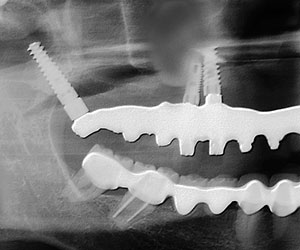

Rx panorámica postoperatorio inmediato de la colocación del implante pterigoideo

A los meses de espera de la osteointegración de los implantes, se procedió a la rehabilitación total de la cavidad oral, logrando devolverle a la paciente estabilidad, estética y función.